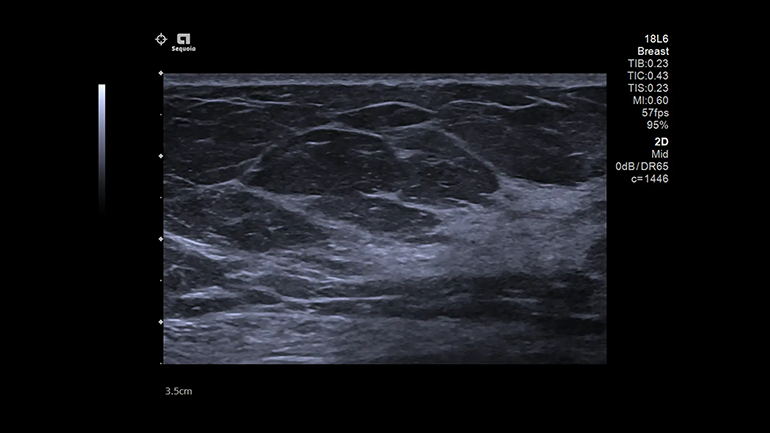

ACUSON Sequoia — новая ультразвуковая система Siemens Healthineers, созданная с учетом потребностей врачей и пациентов. В основе УЗ-системы ACUSON Sequoia лежит технология BioAcoustic, которая способна снизить влияние вариабельности пациентов на ультразвуковую диагностику. Благодаря этому ACUSON Sequoia позволяет эффективно получать важную диагностическую информацию.

Система Acuson Sequoia учитывает биоакустические вариации каждого пациента – это характеристики, включающие плотность ткани, и способность к поглощению и рассеянию сигнала. Система обеспечивает визуализацию тканей с высоким разрешением во всем поле зрения. Таким образом, специалисту не требуется корректировать зону фокуса сканера, а это ускоряет исследование без потери качества. Кроме того, новая система обеспечивает цветное допплеровское картирование кровотока с высоким разрешением, чувствительностью и глубиной проникновения (в среднем на 20% выше, чем у других систем).

Мощная архитектура УЗ-системы ACUSON Sequoia устраняет необходимость в формировании обычных зон фокуса и позволяет создавать полностью сфокусированные изображения превосходного качества на всей глубине сканирования. В технологии InFocus используются синтезированные, ретроспективно фокусируемые УЗ-лучи, распространяющиеся по всему полю обзора, которые фокусируются на любых глубинах. Из обычной передающей последовательности сигналов собирается больше информации за счет использования массивных перекрывающихся многолучевых групп, а не отдельных лучей или пучков параллельных УЗ- лучей, как в обычных диагностических системах.

В системе ACUSON Sequoia реализована технология коррекции скорости звука, которая изменяет скорость ультразвуковых волн в зависимости от типа ткани или патологии. Это позволяет улучшить фокусировку, пространственное и контрастное разрешение изображений.